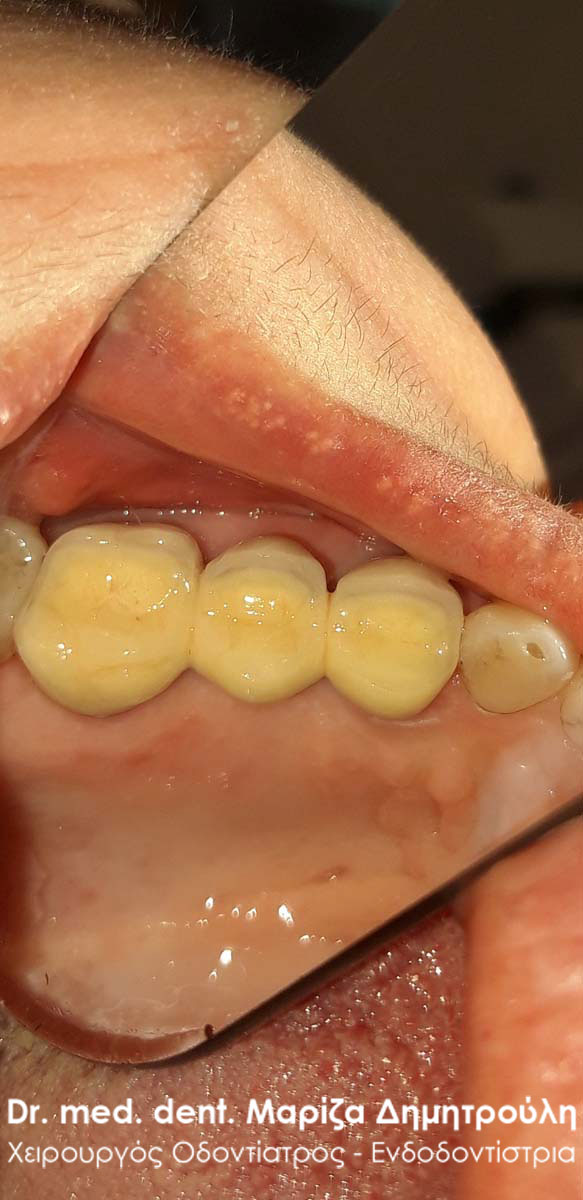

Τελική κλινική εικόνα με την ολοκεραμική θήκη δοντιού